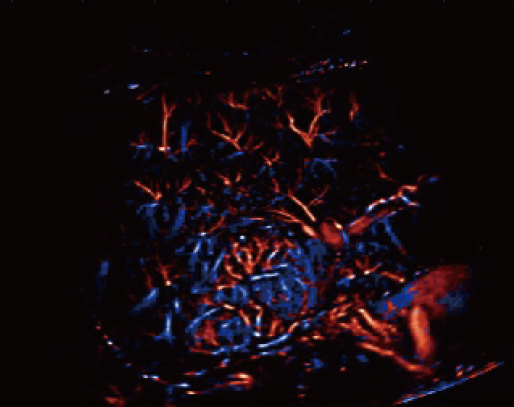

Resona A20 supports clinicians in cutting-edge clinical research. Super

Resolution CEUS (SR CEUS) reveals blood perfusion details at the micron

level, aiding clinicians in the exploration of early microcirculatory

changes in lesions. Additionally, STVi shear wave viscoelastography, a

Powered by the AIT platform, the Resona A20 delivers an all-in-one

integrated solution for super-resolution imaging, a capability

previously difficult to achieve. SR CEUS reveals the intricate

microcirculation details of lesions at the micron level, aiding in

microcirculatory perfusion studies in oncology.

Microvascular detection capabilities

Focal Nodular Hyperplasia | Velocity Map